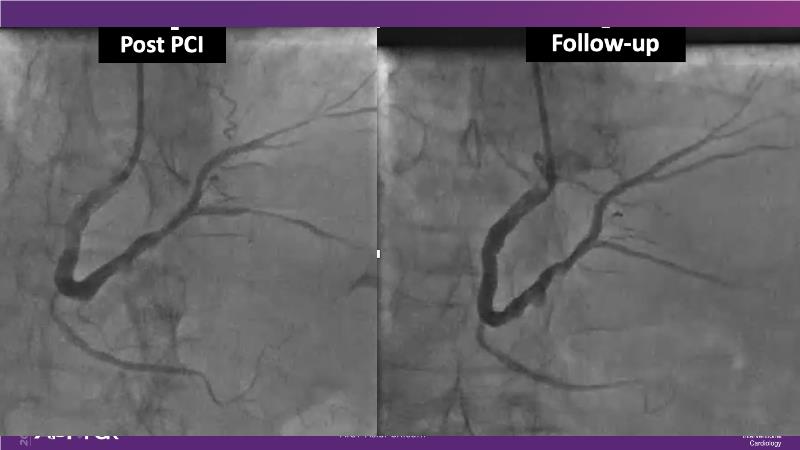

Sirolimus coated balloon: expanding the scope of coronary artery disease treatment

Consult this session to understand the technology and scientific evidence of the novel sirolimus drug-coated balloon, to learn its utility for PCI in a variety of lesion and patient subsets and to understand the evidence and outcomes in real-world patients.

- To understand the technology and scientific evidence of the novel sirolimus drug-coated balloon (SDCB)

- To learn the utility of the DCB for PCI in a variety of lesion and patient subsets

- To understand the evidence and outcomes of this DCB in real world patients